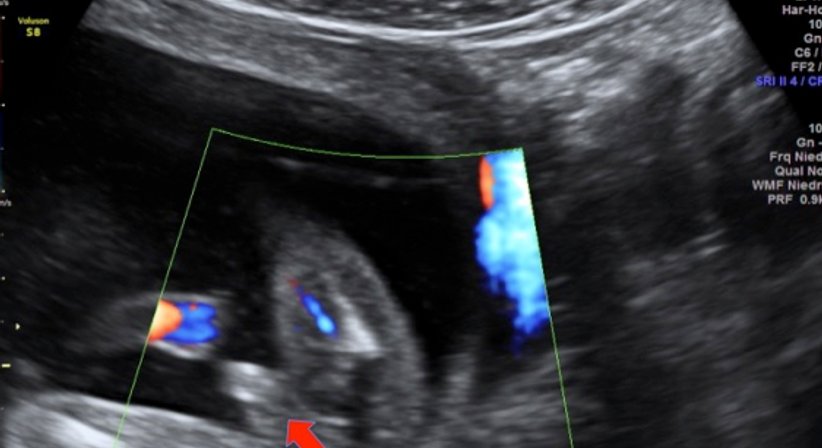

Wir verfügen seit 2015 über ein extrem hochwertiges Ultraschallgerät, das neben einer sehr guten Bildauflösung Techniken wie 3D Ultraschall, 4D Ultraschall und verbesserten Dopplerultraschall bietet. Ich selbst bin für diese Techniken sowie die Nackenfaltenmessungen (in der Frühschwangerschaft) zertifiziert. Bilder und Filme werden auf Wunsch auf einen USB-stick gespielt, sodass man diese mit nach Hause nehmen kann.

Bei nahezu allen gynäkologischen Untersuchungen mache ich natürlich auch eine Ultraschalluntersuchung des kleinen Beckens. Durch die sog. Vaginalsonde kann man sämtliche Strukturen exakt darstellen und mit der Patientin besprechen. Vor allem bei Eierstockzysten, Menstruationsstörungen und bei entzündlichen Veränderungen, wie Abszessbildungen u.a. ist der Ultraschall äußerst wichtig.

Mit verschiedenen Methoden können wir heute beurteilen, ob während der Schwangerschaft mit Mutter und Kind alles in Ordnung ist, oder ob Risiken vorliegen. Der Ultraschall hilft uns dabei als nahezu einzige Methode, das ungeborene Kind in der Gebärmutter direkt sichtbar zu machen.